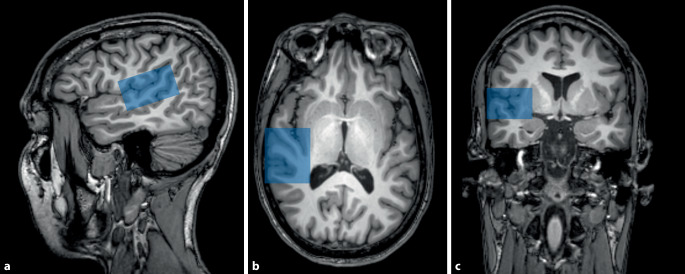

Funktionelle MRT

Mittels einer BOLD(Blood-Oxygenation-Level-Dependent)-Sequenz lässt sich das Verhältnis zwischen oxygeniertem und desoxygeniertem Blut nachweisen. Dies lässt Rückschlüsse auf Bereiche im Gehirn mit hoher Aktivität zu. Die Auflösung ist dabei sowohl zeitlich auf einige Sekunden als auch räumlich auf einige Millimeter begrenzt und sollte als Aktivität für bestimmte Regionen interpretiert werden [7]. Die Hirnaktivität kann in Ruhe („Resting-State-fMRT“) oder während der Erledigung einer Aufgabe („Task-Based-fMRT“), im Fall von Tinnitus am ehesten im Sinne einer auditiven Aufgabe, erfasst werden. Bei der Resting-State-fMRT werden die spontanen Aktivitäten im Gehirn gemessen. Diese verlaufen entlang von Bahnen, welche verschiedene Hirnregionen funktionell verknüpfen. Dabei entstehen Netzwerke, („resting state networks“) welche die funktionellen Zusammenhänge verschiedener Regionen aufzeigen, bei denen die neuronale Aktivität zeitlich korreliert ist (Abb. 1).

Die funktionelle Magnetresonanzspektroskopie des Gehirns (fMRS) nutzt die MRT, um den Stoffwechsel im Gehirn zu untersuchen. Anstelle einer Aktivität, wie bei der funktionellen MRT, kann die Konzentration von bestimmten Metaboliten in vorher definierten Bereichen (ROI, „region of interest“) des Gehirns gemessen werden. Es wird zunehmend als wichtiges Werkzeug in den Neurowissenschaften etabliert, um die Hirnfunktion unter normalen und pathologischen Zuständen zu untersuchen. Bei Tinnitus konnten auf Basis von Tierversuchen schon verschiedene Metaboliten aufgezeigt werden, welche eine veränderte Konzentration in bestimmten Hirnarealen aufweisen [3]. Dank der fMRS ist eine solche Analyse auch bei Menschen in vivo möglich.

Neuronale Netze verändern sich mit der Tinnituswahrnehmung

Während Tinnitus weitestgehend im Ohr beginnt, sind auch Elemente der zentralen Hörbahn im Hirnstamm sowie der Hörrinde im Gehirn (auditorischer Kortex; Abb. 2) an der Aufrechterhaltung des Tinnitus beteiligt. Diese neuronalen Netze verändern sich mit der Tinnituswahrnehmung und beeinflussen die Zusammensetzung von Stoffwechselprodukten und Zellen in bestimmten Gebieten des Gehirns. Es gibt Hinweise darauf, dass die Tinnituswahrnehmung auch durch eine fehlende Inhibition (Unterdrückung) von Teilen dieser Netze aufrechterhalten wird [35]. Verdächtigt wird etwa ein Mangel an dem inhibitorischen Neurotransmitter Gamma-Aminobuttersäure (GABA) im auditorischen Kortex oder eine erhöhte Konzentration von exzitatorisch wirkendem Glutamat [15, 36]. In verschiedenen Tierstudien wurden bereits Unterschiede zwischen Konzentrationen solcher Neurotransmitter im auditorischen Kortex aufgezeigt [41]. In der Anwendung von fMRS bei Tinnitus zeigte sich eine reduzierte Konzentration des inhibitorisch wirkenden Neurotransmitters GABA im auditorischen Kortex, was eine erhöhte Spontanaktivität und somit eine weitere Grundlage in der Wahrnehmung von Tinnitus erklären könnte [36].